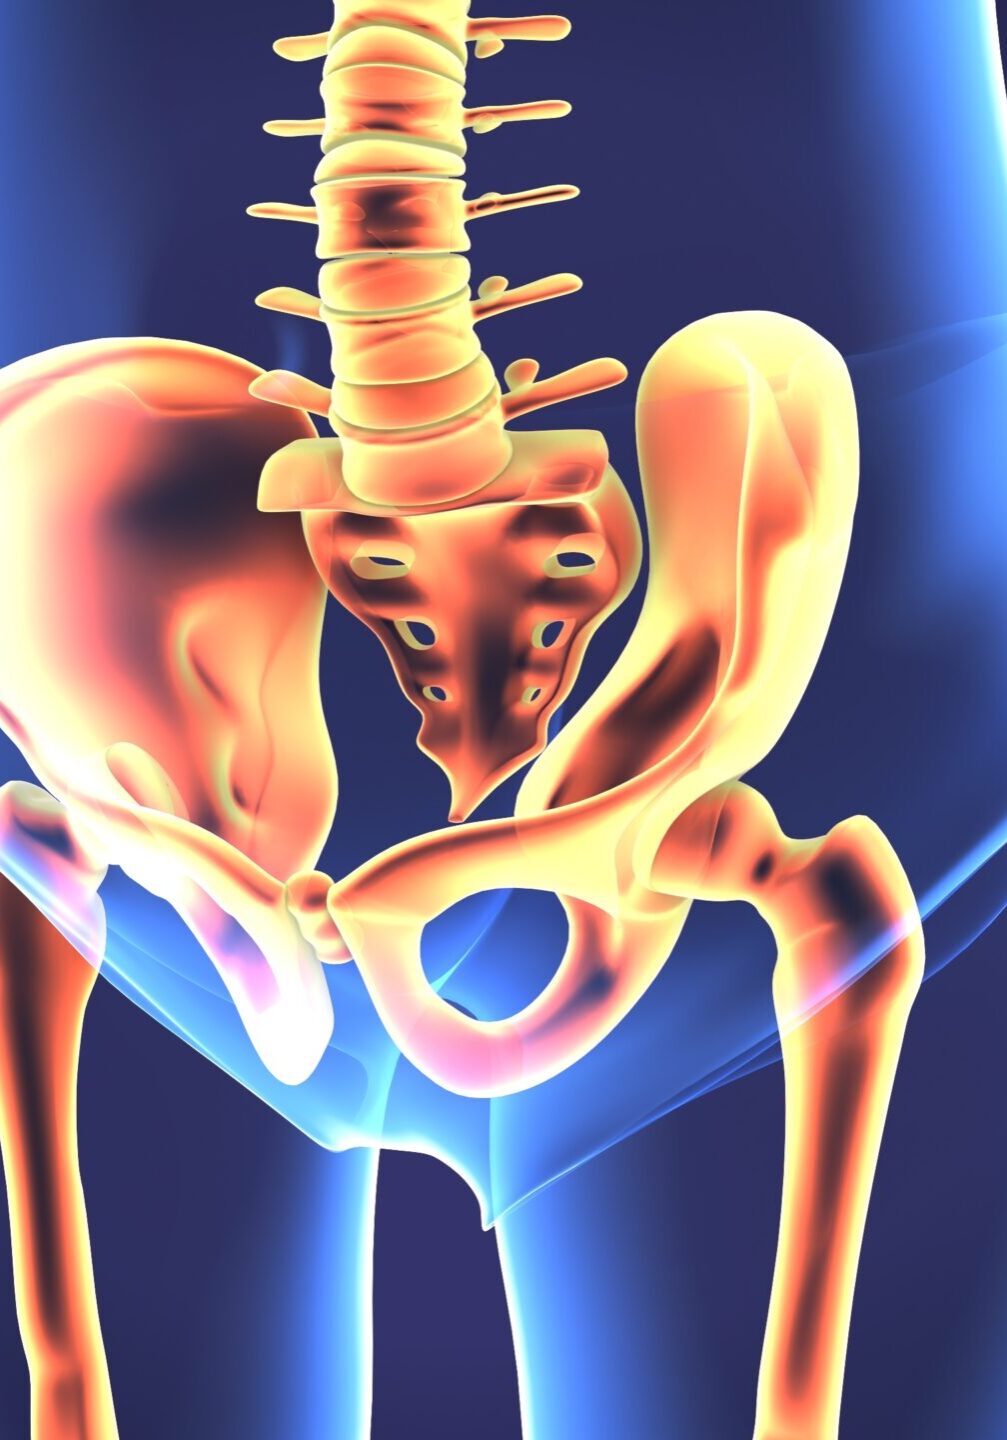

3d illustration of human body hip joint anatomy

Joint restrictions between the bones that make up the pelvis. The pelvis is made up of 3 main bones - two innominates on either side and your tailbone (the sacrum) in the middle.